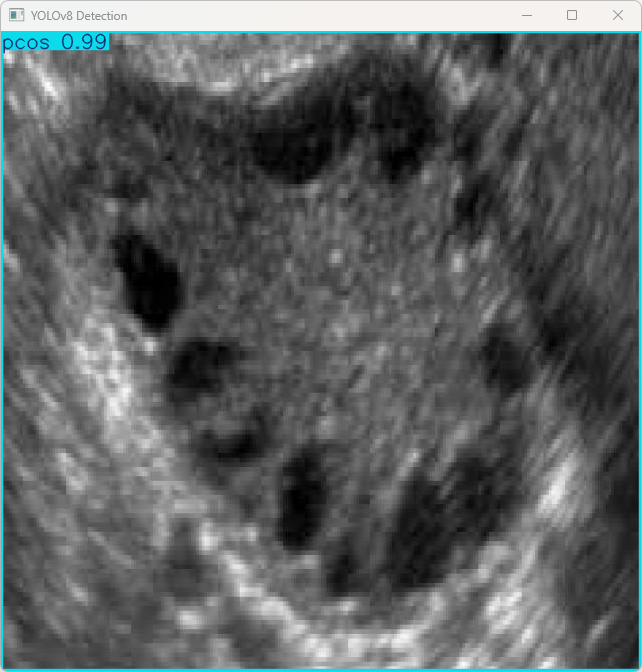

执行imgTest.py代码后,会将执行的结果直接标注在图片上,结果如下:

这段输出是基于YOLOv8模型对图片“imagetest.jpg”进行检测的结果,具体内容如下:

图像信息:

(1)处理的图像路径为:TestFiles/imagetest.jpg。

(2)图像尺寸为640×640像素。

检测结果:

(1)1个PCOS对象,多囊卵巢综合症。

处理速度:

(1)预处理时间: 4.2 毫秒

(2)推理时间: 6.5 毫秒

(3)后处理时间: 102.1 毫秒

总结:

模型在推理时的表现非常好,检测出了PCOS,且推理过程非常快速,适合实时监控与检测。